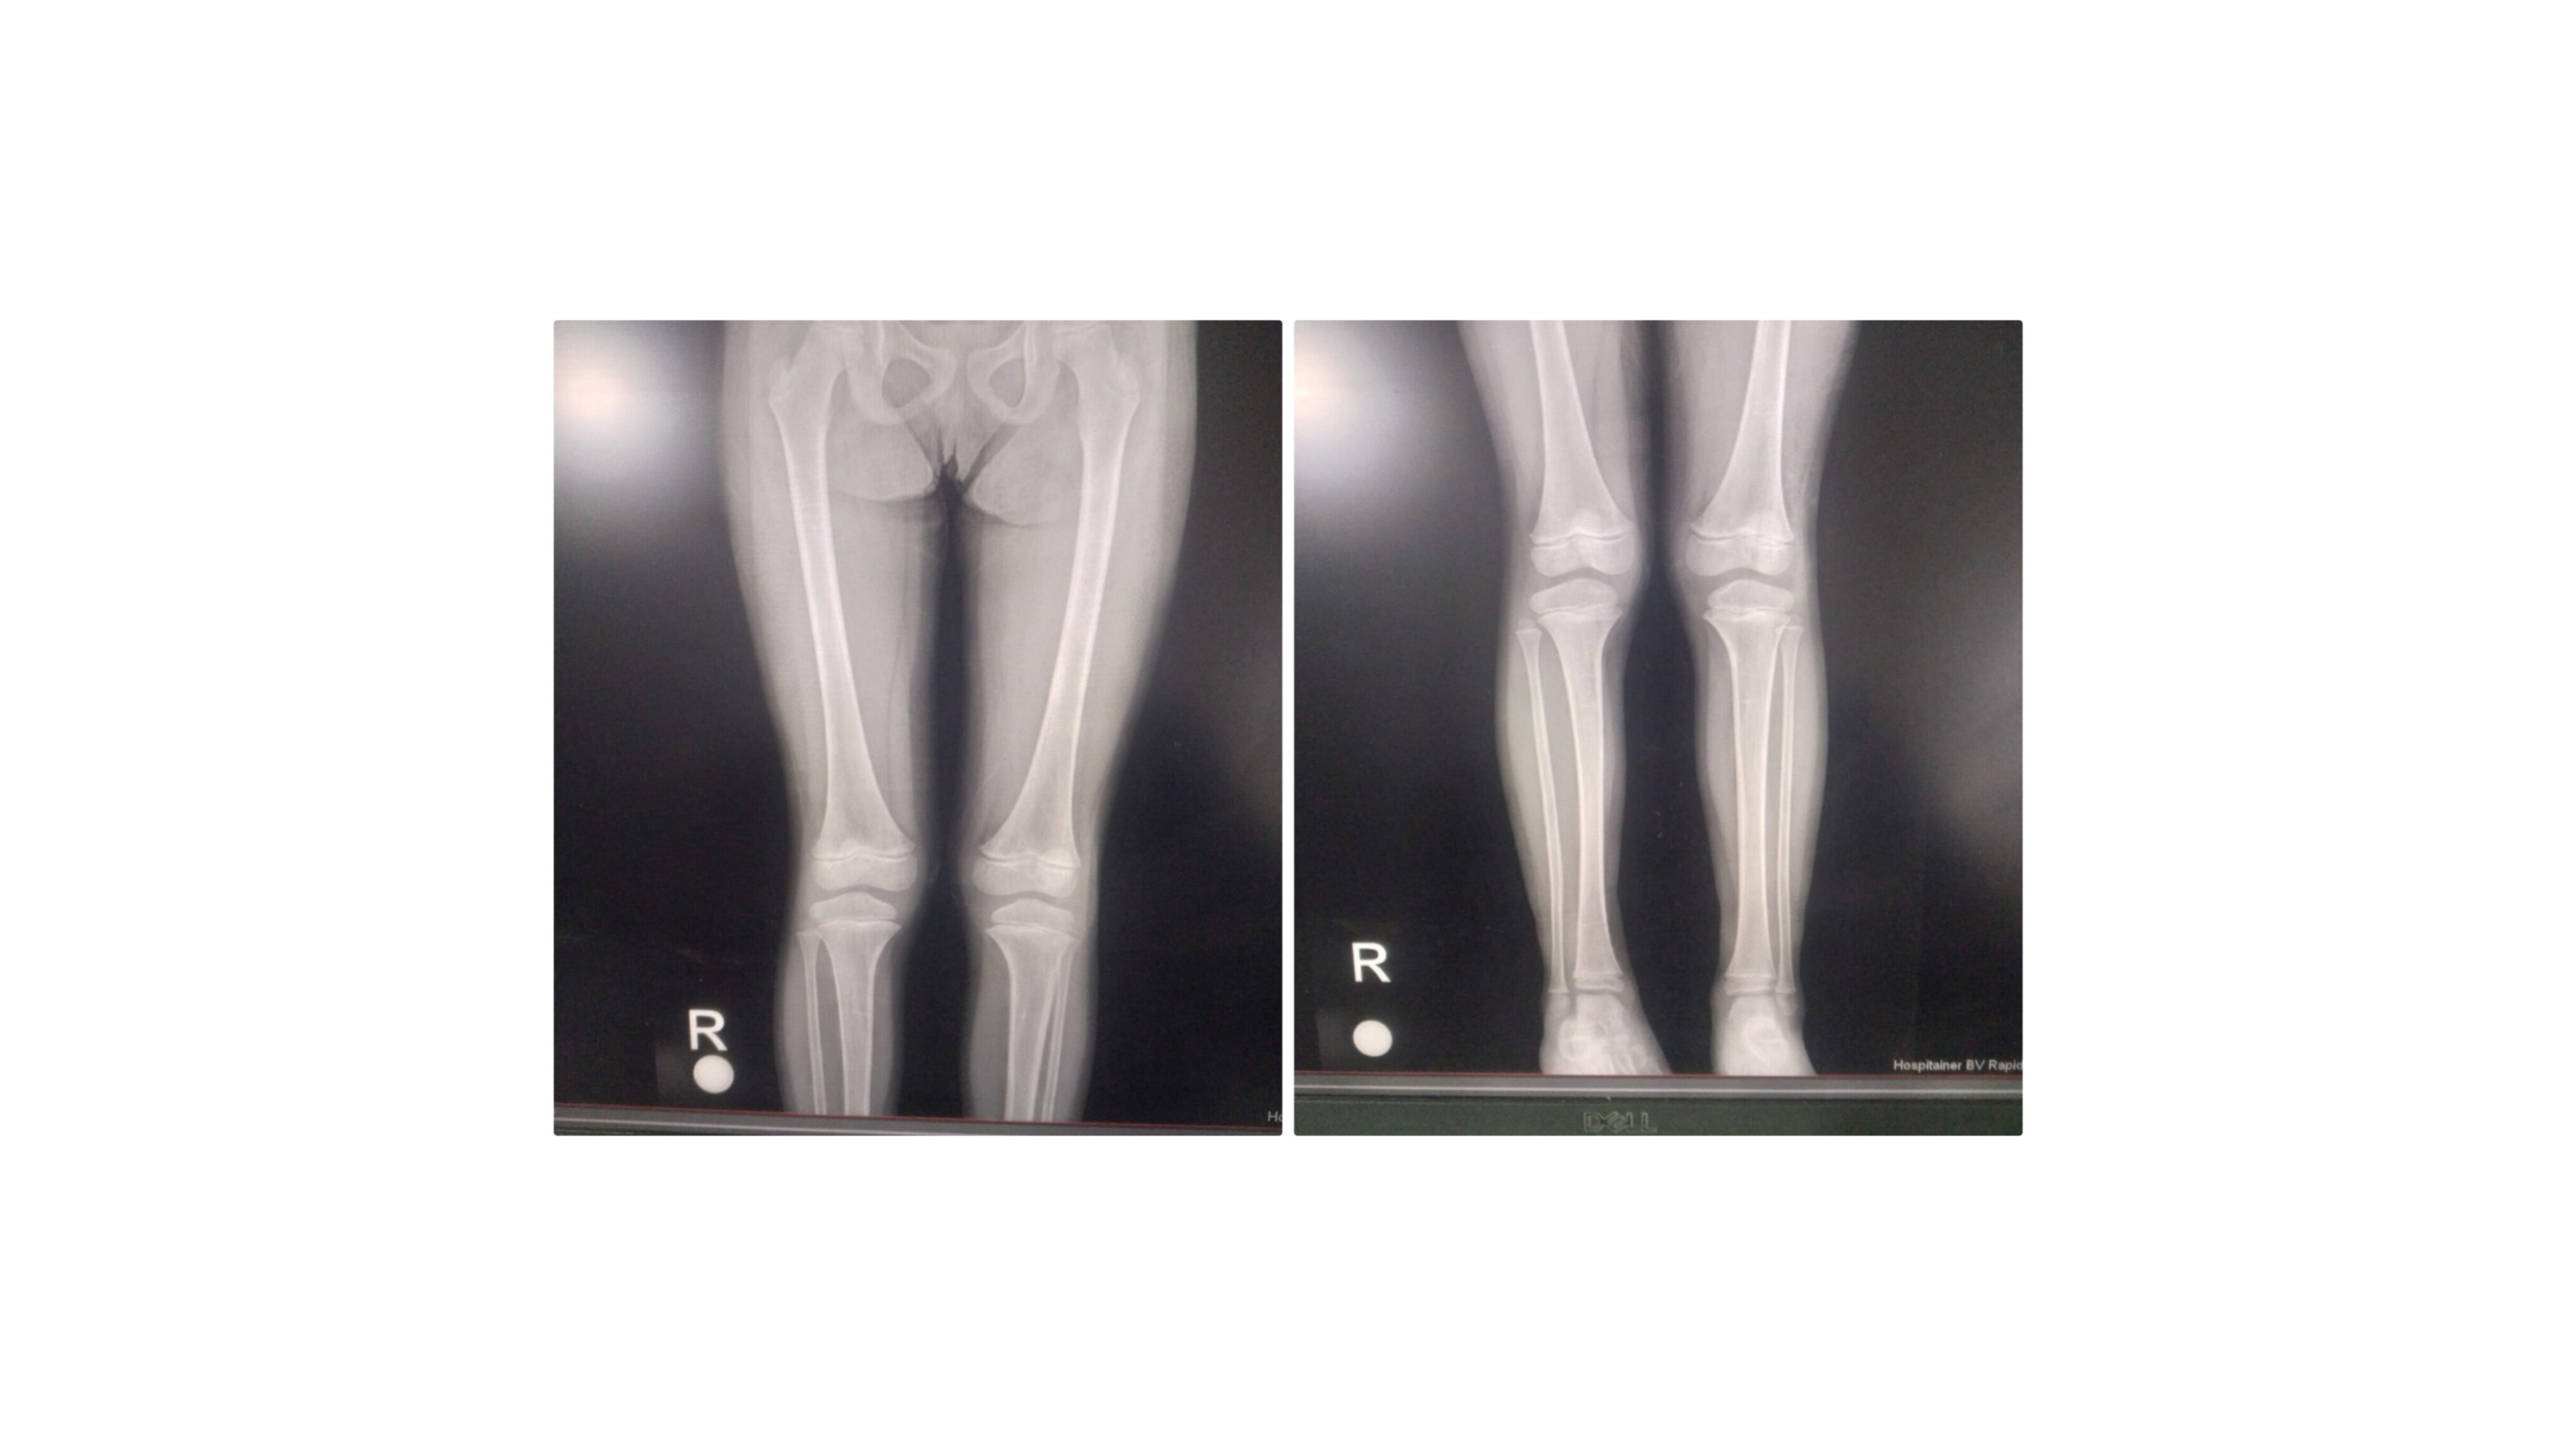

My middle daughter, Iman, was born with a deformity in her right foot and needs a special medical device to walk — but we cannot afford it due to the war, the siege, and the unbearable cost of healthcare.

Get proper treatment for Iman and buy her the medical device she urgently needs